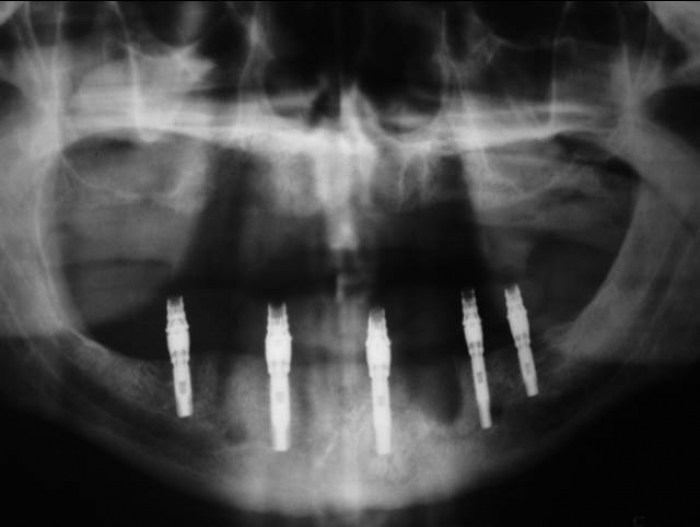

Raio X com 05 Implantes Instalados